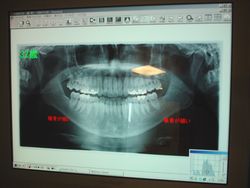

●デジタルX線装置 |

最新デジタル装置になり、従来のX線装置に比べ、最大1/10に放射線照射量を低減します。

それにより患者様の負担が無くなります。